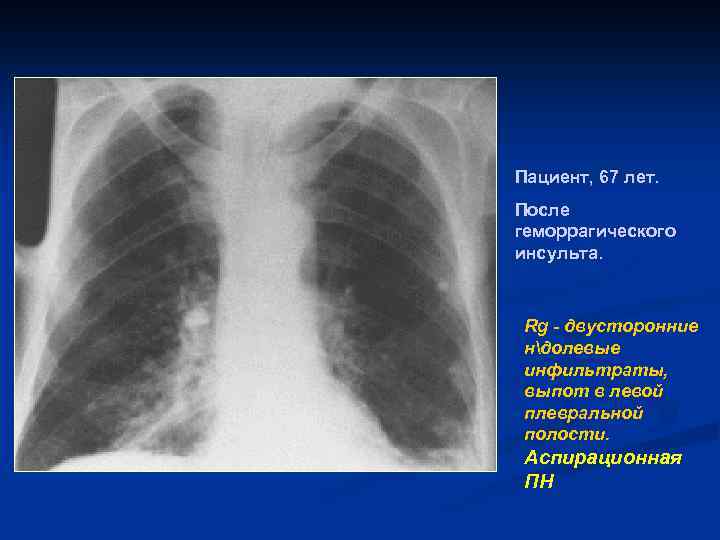

Пациент, 67 лет. После геморрагического инсульта. Rg - двусторонние ндолевые инфильтраты, выпот в левой плевральной полости. Аспирационная ПН